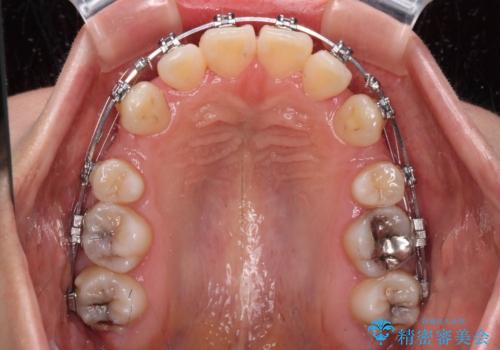

- メタルブラケット

- 2年4ヶ月

- 10-30回

- 口元の突出感を気にして来院された患者様です。

口元を積極的に引っ込めるために、上下左右の第一小臼歯を4本抜歯することとし、ワイヤー装置による矯正治療を行うこととしました。